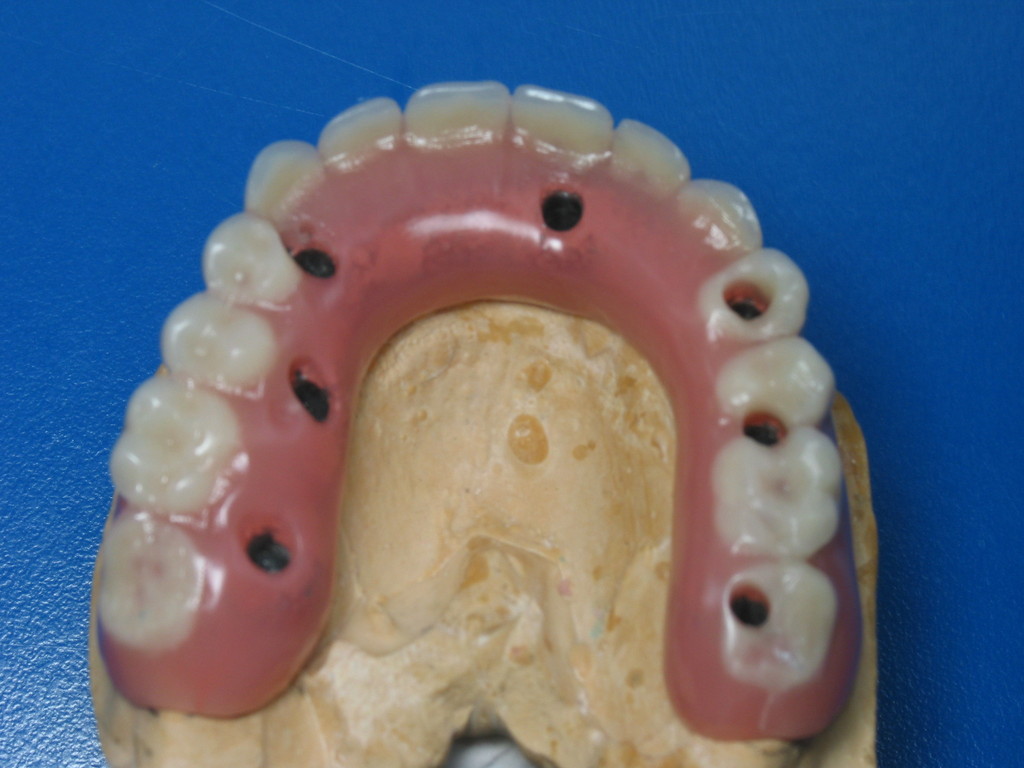

REHABILITACIÓN IMPLANTOSORTADA CERAMOMETÁLICA. POSEXTRACCION

Prótesis definitíva en metal cerámica